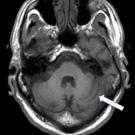

Farah Khan, MD; Richard H. Schwartz, MD, DO; Rebecca Levorson, MD

A 2-year-old girl was diagnosed with S dysgalactiae brain abscess, meningitis, and cerebritis, possibly from a recent middle ear infection.